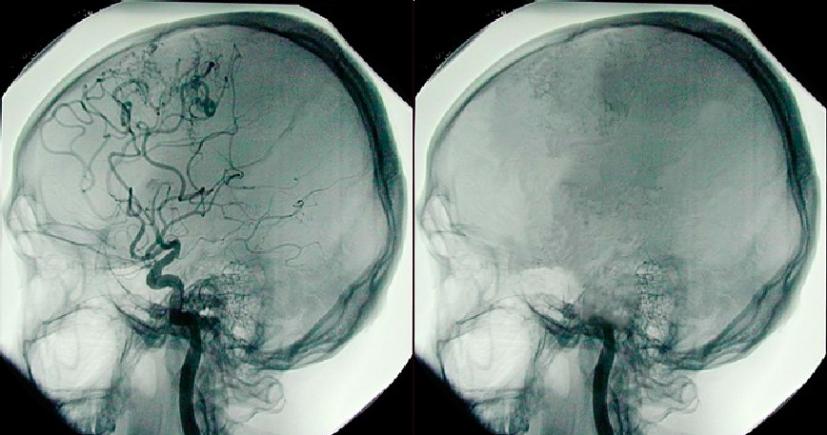

«Τώρα αν οι εγκεφαλικές λειτουργίες των ανθρώπων μοιάζουν με αυτές των ποντικών αυτή είναι μια ερώτηση του ενός εκατομμυρίου» αναφέρει ο νευρό επιστήμονας Jimo Borjigin του πανεπιστημίου του Μίτσιγκαν. Επίσης τονίζει πως τόσο καιρό οι γιατροί εστιάζουν στο να διατηρήσουν την καρδιά ζωντανή ώστε να συνεχίσει η λειτουργία του εγκεφάλου.Μήπως θα έπρεπε να εστιάσουμε να κρατάμε ζωντανό τον εγκέφαλου και να ρυθμίσουμε τις εντολές που στέλνει ώστε να διατηρηθεί και η καρδιά ζωντανή? – ρωτάει..